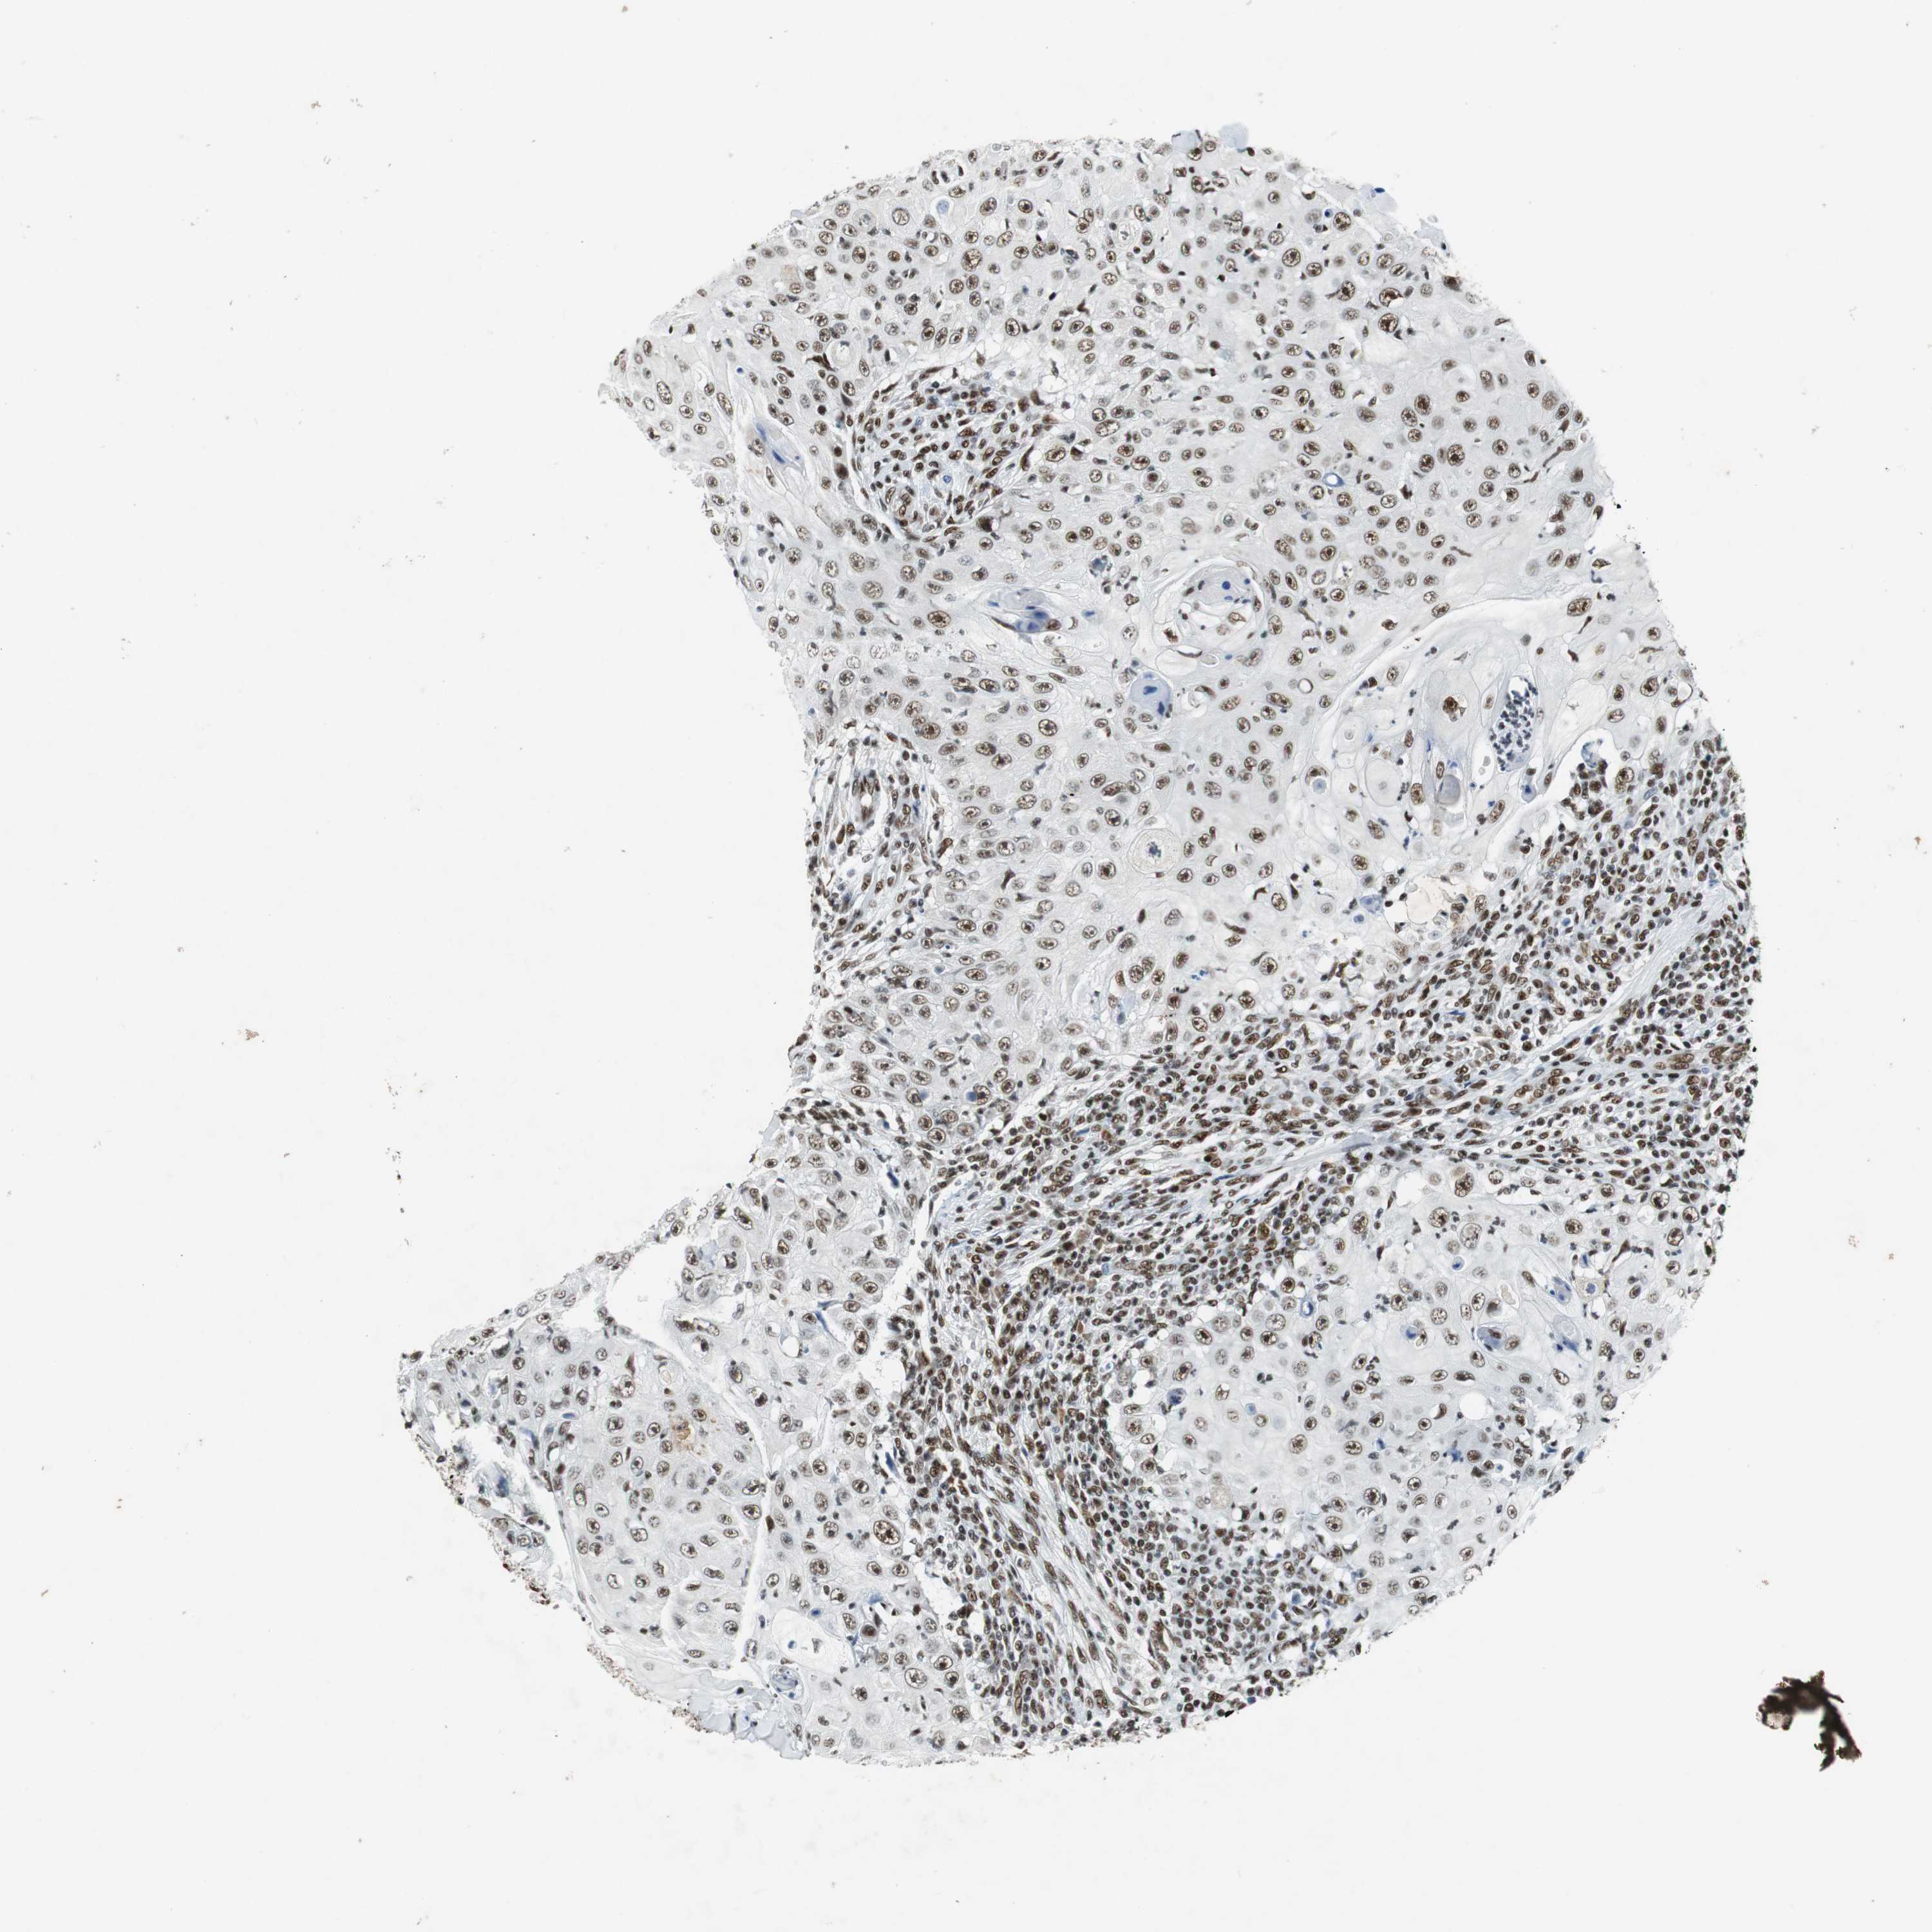

SKIN CANCER - Protein expressioni

A mouse-over function shows sample information and annotation data. Click on an image to view it in a full screen mode. Samples can be filtered based on level of antibody staining by selecting one or several of the following categories: high, medium, low and not detected. The assay and annotation is described here.

Antibody staining in the annotated cell types in the current human tissue is reported as not detected, low, medium, or high, based on conventional immunohistochemistry profiling in selected tissues. This score is based on the combination of the staining intensity and fraction of stained cells.

Each image is clickable and will lead to virtual microscopy that enables deeper exploration of all samples and also displays staining intensity scores, fraction scores and subcellular localization as well as patient and tissue information for each sample.

Antibody HPA035174

Antibody CAB005167

Staining

High

Medium

Low

Not detected

Intensity

Strong

Moderate

Weak

Negative

Quantity

>75%

75%-25%

<25%

None

Location

Nuclear

Cytoplasmic/membranous

Cytoplasmic/membranous,nuclear

Squamous cell carcinoma, NOS